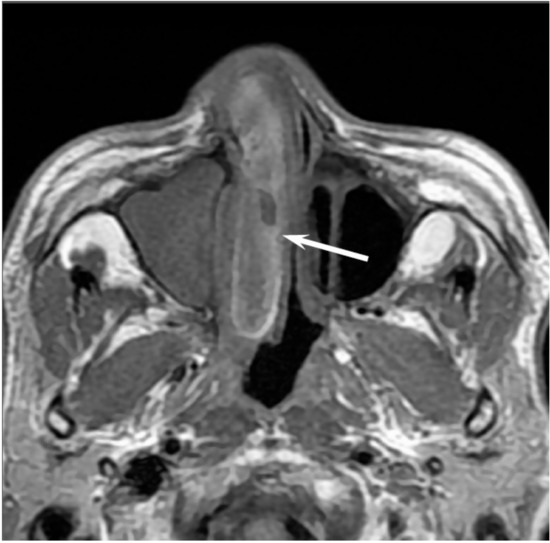

On CT, sinonasal adenocarcinomas appear as a soft-tissue mass and occasionally exhibit areas of calcification, which reflect the mucin content. In unilateral olfactory cleft adenocarcinomas, the bulging of the nasal septum across the midline and widening of the olfactory cleft are observed [15]. High-grade adenocarcinomas often show bone destruction. Adenocarcinomas arising from the ethmoid sinus may potentially extend to the skull base and intracranially to the frontal lobes [16]. On MRI, the signal intensity of the adenocarcinomas varies according to their mucin content, cellularity and the presence of hemorrhage. Mucin-producing adenocarcinomas usually show hyperintensity on T2WI and exhibit gradual enhancement on contrast-enhanced T1WI, whereas adenocarcinomas without mucin production show iso- to hypointensity on T2WI. The imaging characteristics of adenocarcinomas are often indistinguishable from those of SCCs (Figure 2).

Figure 2. Non-intestinal type adenocarcinomas of the right maxillary sinus. T2-weighted image showing a heterogeneously hyperintense lesion (arrow).